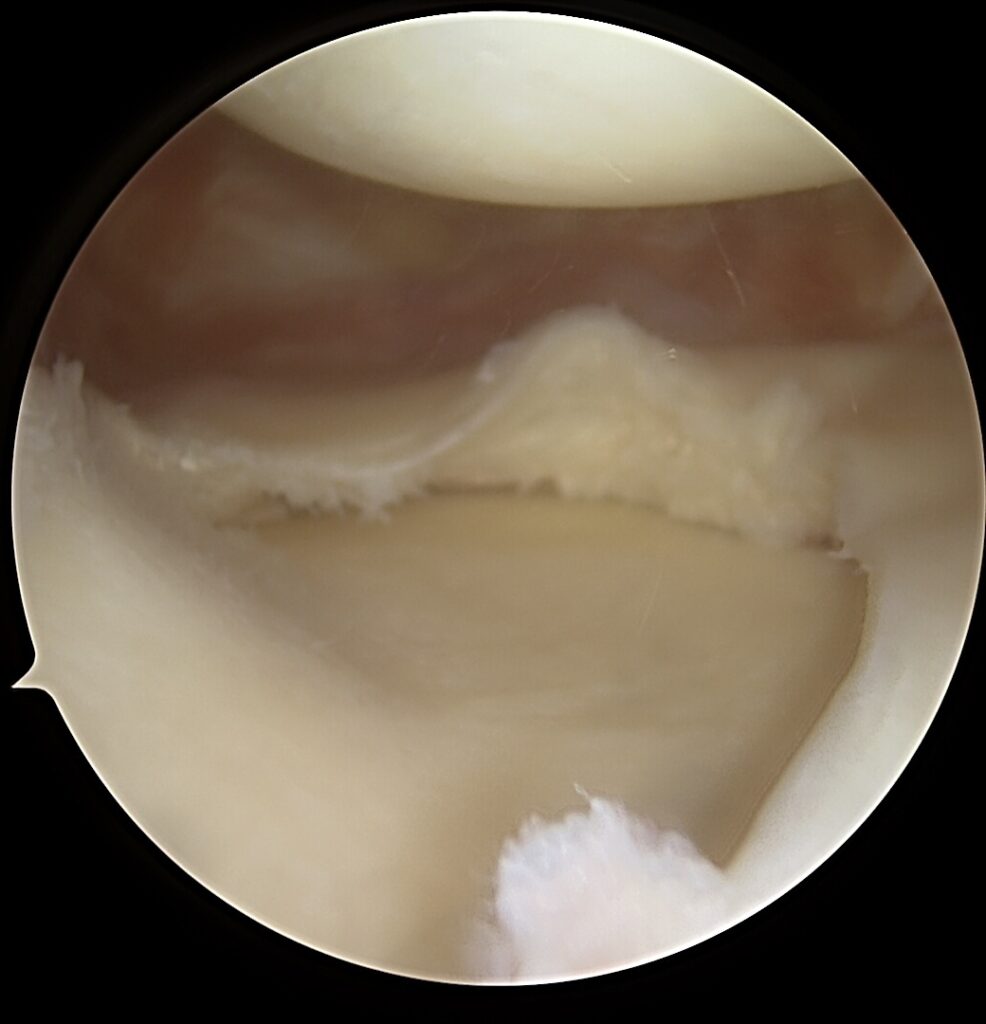

🔎 Dažniausiai pažeidžiamos struktūros:

- Priekinis kryžminis raištis (ACL)

- Užpakalinis kryžminis raištis (PCL)

- Posterolateralinis kampas (PLC)

- Vidinis kolateralinis raištis (MCL)

- Įstrižinis raištis (POL)

Be kompleksinio chirurginio gydymo kelias tampa nestabilus, skausmingas, sparčiai vystosi ankstyva artrozė.